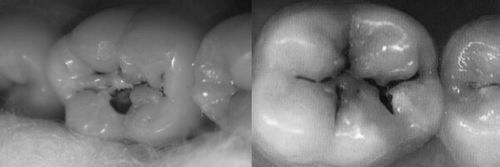

Зуби при захворюванні покриваються спочатку безбарвним, а потім і темним нальотом, стоншуються, в них з'являються маленькі дірочки, які без належного лікування можуть привести до остаточної їх псування і навіть випадання.

- виникнення білих, а потім і темних плям на білій емалі,

- виникнення маленьких дірочок,

Зовні визначити перехід симптомів до поверхневої стадії можна по появі невеликих чорних і коричневих плям, дефектів емалі і збільшення жовтого, або білого нальоту.

Але нерідкі випадки, коли плям практично немає, а є тільки невелика тріщинка, при уважному огляді якої лікар-стоматолог констатує передостанню стадію карієсу, що пов'язано з тим, що поверхня досить тверда і вразити її хвороби складніше, ніж проникнути в м'які тканини, звані дентином .

Зовні глибокий карієс нічим не відрізняється від симптомів хвороби на попередній стадії, але область поразки емалі та дентину чорними плямами може розширитися.